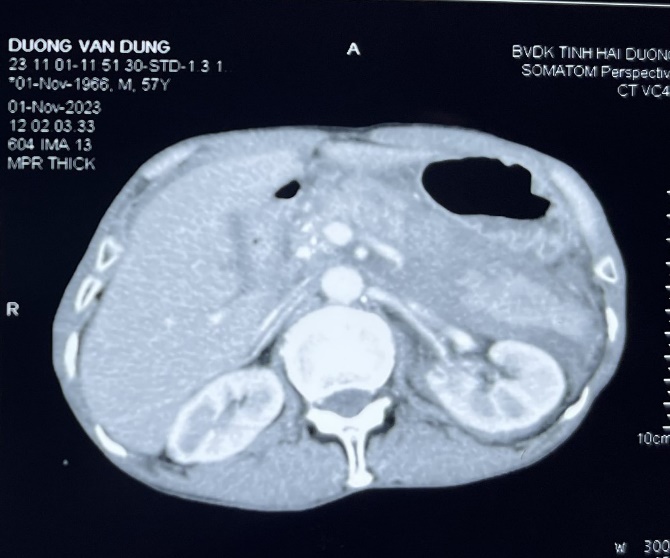

Chụp CLVT ổ bụng lần 1: Hình ảnh chấn thương tụy độ III. Chấn thương thận trái độ II. Hình ảnh đám tụ máu khoang sau phúc mạc. Dịch ổ bụng. Nốt vôi hóa vùng đầu tụy. Giãn nhẹ đường mật gan trái. Sỏi túi mật.

Chụp CLVT ổ bụng lần 2 sau 1 ngày: Kết quả như trên.

Chúng tôi quyết định mổ cấp cứu bệnh nhân với chẩn đoán: CTBK – Vỡ tụy độ III- TD đứt đôi tụy. Tụ máu lớn hậu cung mạc nối/CT thận trái độ 2 TD chấn thương ngực.